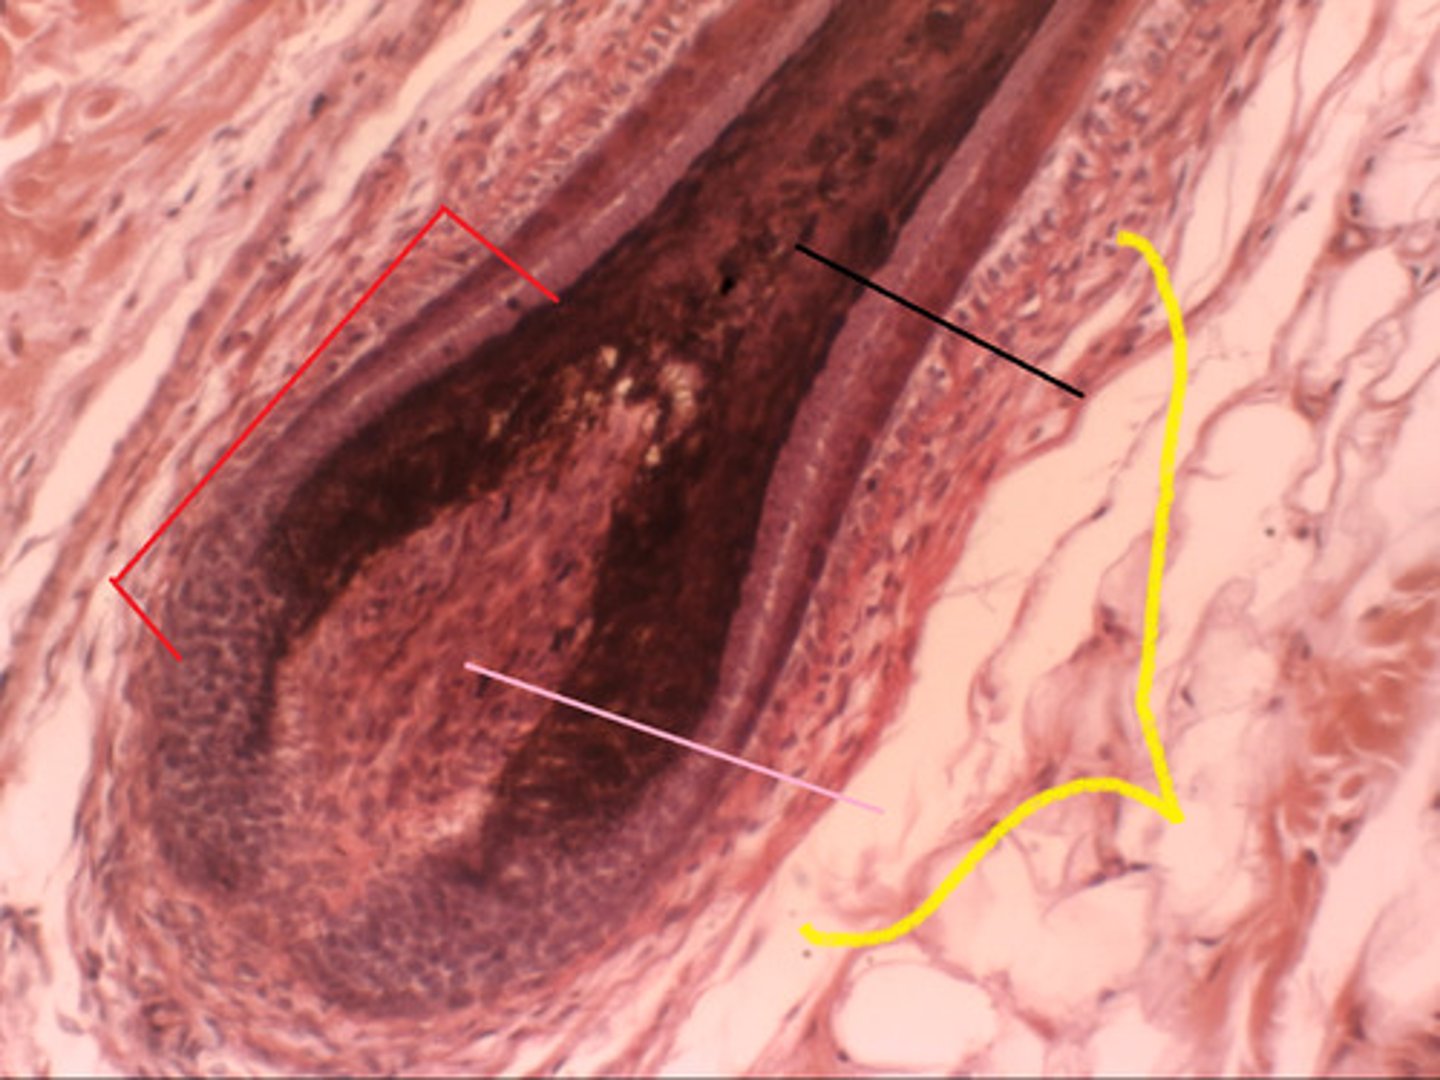

hair follicle

<p>a small tubular cavity containing the root of a hair</p>

hair matrix

<p>actively dividing area of the hair bulb that produces the hair</p>

hair bulb

<p>The rounded, club-shaped part of hair located at the end of the hair root</p>

hair papilla

<p>mass of connective tissue, blood capillaries, and nerve endings at the base of the hair follicle</p>

arrector pili muscle

<p>An involuntary muscle fiber attached to the underside &amp; base of the hair follicle</p>

sebaceous glands

<p>secrete sebum (oil) into the hair follicles where the hair shafts pass through the dermis</p>